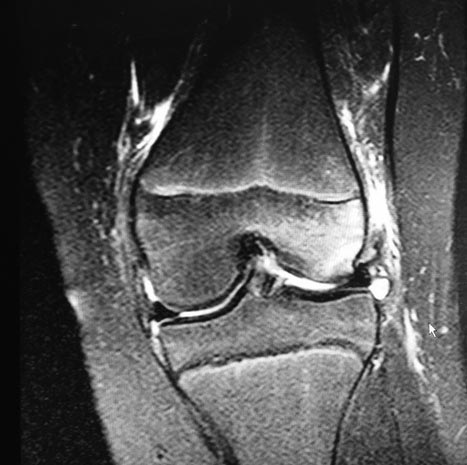

Девочка 10 лет. Травма 1 месяц назад упала на горке. Лечилась

консервативно. По данным МРТ имеется остеохондральный дефект наружного

мыщелка бедренной кости и свободный костно-хрящевой фрагмент размером 3

см. в диаметре. План лечения: артротомия, рефиксация по возможности. На